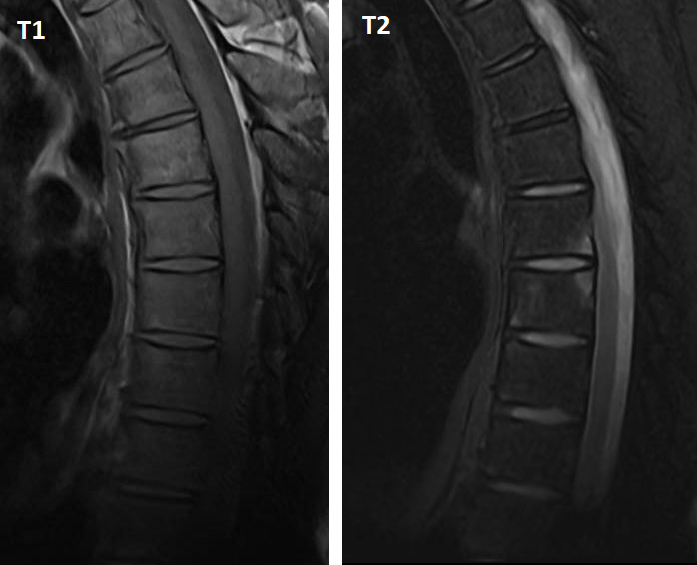

Voici des IRM en séquences T1 et T2 avec suppression du signal de la graisse (Dixon water) :

Figure 2 (Salomé Abdellaoui, La Revue du Praticien)

L’IRM rachidienne montre de nombreux coins inflammatoires en hypersignal T2, qui témoignent d’une atteinte enthésitique au rachis. On les distingue des coins « graisseux » qui apparaissent en hypersignal T1 et en hypersignal T2 ou iso-signal sur les séquences avec suppression du signal de la graisse.